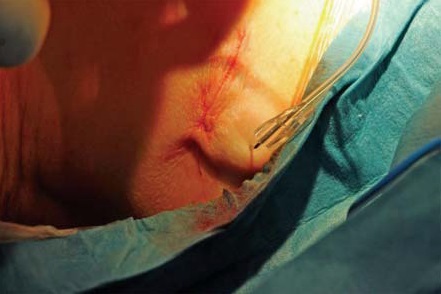

Методика имплантации. Пациенту выполнена люмбальная пункция в проекции L1-сегмента иглой Туохи парамедианным доступом. Интратекально в краниальном направлении заведен спинальный катетер на 6 см. Проведена морфиновая проба (в субарахноидальное пространство введено 100 мкг морфина). Через несколько минут пациент отметил уменьшение болевого синдрома по НОШ с 80 до 10%. На этом фоне пациент смог безболезненно повернуться на спину. Морфиновая проба рассмотрена как положительная, имплантирована порт-система «B|Braun Celsitest 304-20». Камера порта выведена подкожно по передней подмышечной линии в проекции пятого межреберья. Последовательность ключевых этапов манипуляции представлена на рисунках 1–8.

Рис. 4. Контроль положения дистального кончика катетера (аспирационная проба), выполнение морфиновой пробы

Рис. 6. Фиксация спинального катетера к камере порта, контроль проходимости системы (аспирационная проба)